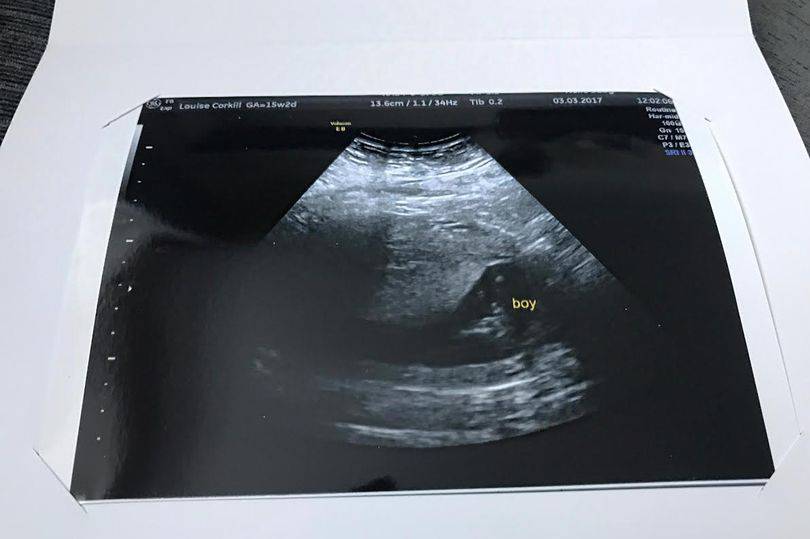

Louise Corkill è una donna inglese di 30 anni, già mamma di un bambino di 11 e di una bambina di 6. Aspetta il suo terzo figlio e ha deciso di pagare per sottoporsi ad una pre morfologica a 15 settimane per vedere il sesso del bambino; convinta che fosse una femmina, è rimasta stupita nell’apprendere che fosse un maschio. La cosa più scioccante è stata però quello che ha visto durante l’ecografia. come è già successo in passato.

Louise quando ha fatto stampare l’immagine dell’eco non credeva ai propri occhi: in un angolo si può vedere chiaramente il volto di sua nonna Maria Parkinson, che è morta nel 2001 a 66 anni. Non appena ha visto l’immagine è rimasta stupita: “Mi sono sentito male e subito iniziato a singhiozzare. Ho capito subito che era la sua faccia ed ero così scioccata di rivederla“.

Louise voleva stampare un’immagine dell’ecografia e non riusciva per via della posizione del bambino: quando ha trovato quella giusta, ha trovato la sorpresa.

Qualcuno ha detto di essere piuttosto scettico e ha pensato che Louise avesse modificato l’immagine con photoshop. Per fugare ogni dubbio Louise ha mostrato l’ecografia originale e allora le persone rimangono stupite: “Una mia collega d’ufficio quasi cadeva dalla sedia“.